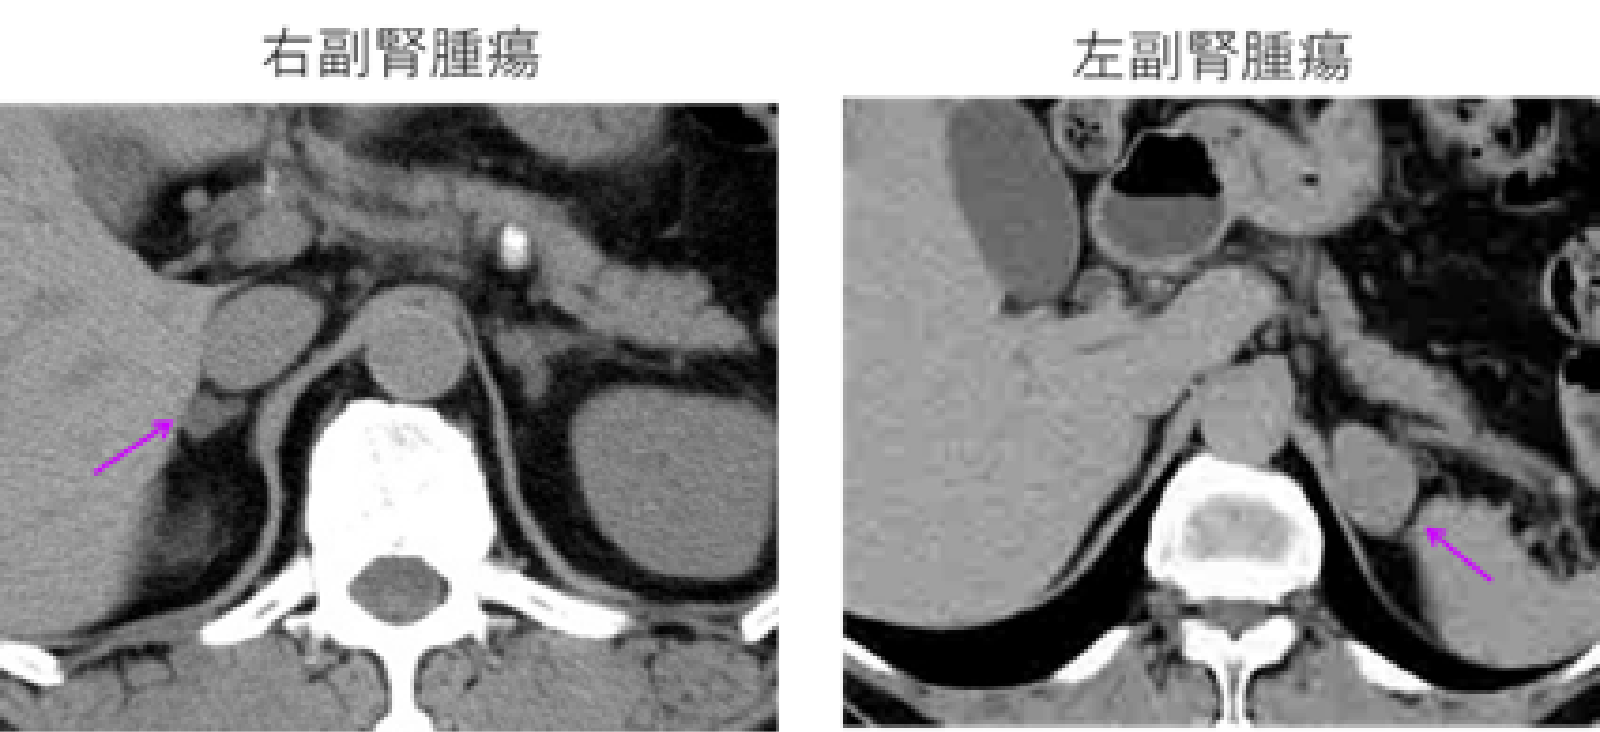

副腎腫瘍はCTではどのように見えますか?

CT スキャンでは、良性の副腎腫瘍または腺腫は、通常、脂肪含有量が高いため、周囲の組織から目立つ、はっきりとした円形または楕円形の病変として現れます。

副腎癌腫としても知られる癌性副腎腫瘍は、大きく不規則な形の塊として現れることがあります。通常、組織の組成が異なるため、密度が不均一で、視認性の低い領域と高い領域があります。

ただし、すべての癌性腫瘍がこのように見えるわけではなく、特定の腫瘍の種類やその他の要因によって外観が異なる場合があります。

癌性腫瘍では、CT スキャン中に血流の増加や造影剤の取り込みの亢進が見られる場合もあります。これは、進行性の腫瘍であることを示唆しています。